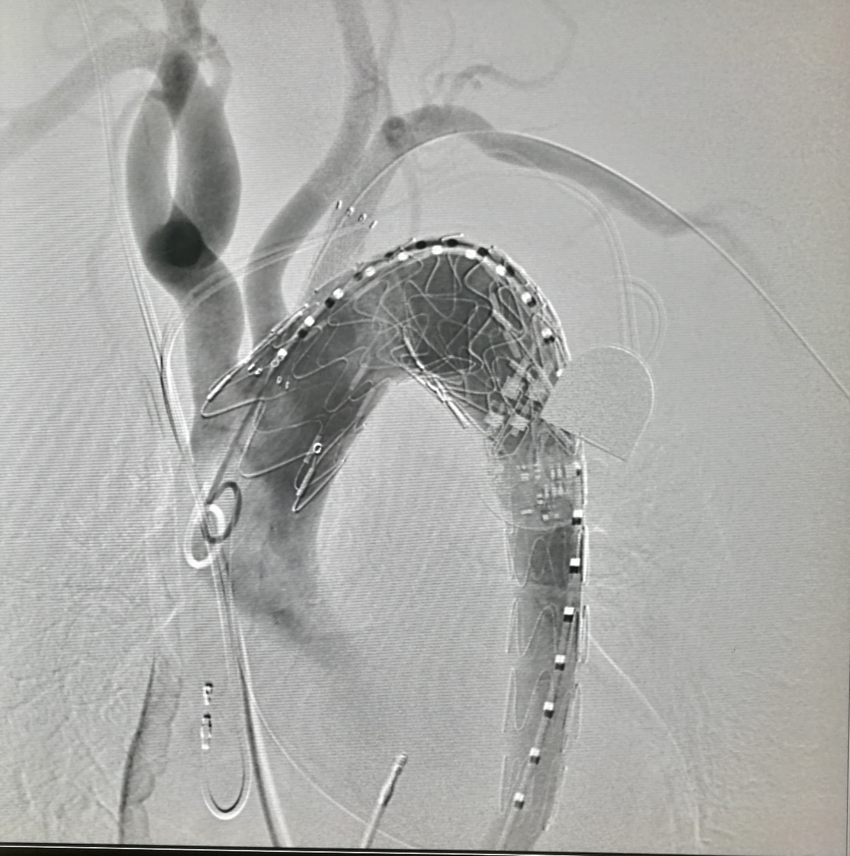

我们在两头35kg巴马公猪中完成动物实验:

成功实现弓上分支的快速、准确原位开窗;

破膜过程流畅,无分支或主动脉损伤;

取出标本可见圆形破口、支架贴合良好,证实技术可行性。

动物实验

巴马公猪35kg

标本